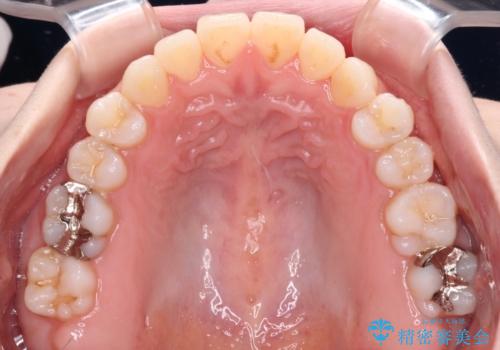

舌突出癖で口元が開いてしまう 舌トレーニングを行ったインビザライン矯正

- インビザライン

- 前歯の上下スペースと前歯の隙間を気にして来院された患者様です。

インビザラインにより上下の前歯の隙間を閉じていくこととしました。

上下の隙間に舌が入り込むことが、すきっ歯やオープンバイトの原因であったため、舌の筋肉のトレーニングも並行して行い、後戻りの抑制を図りました。